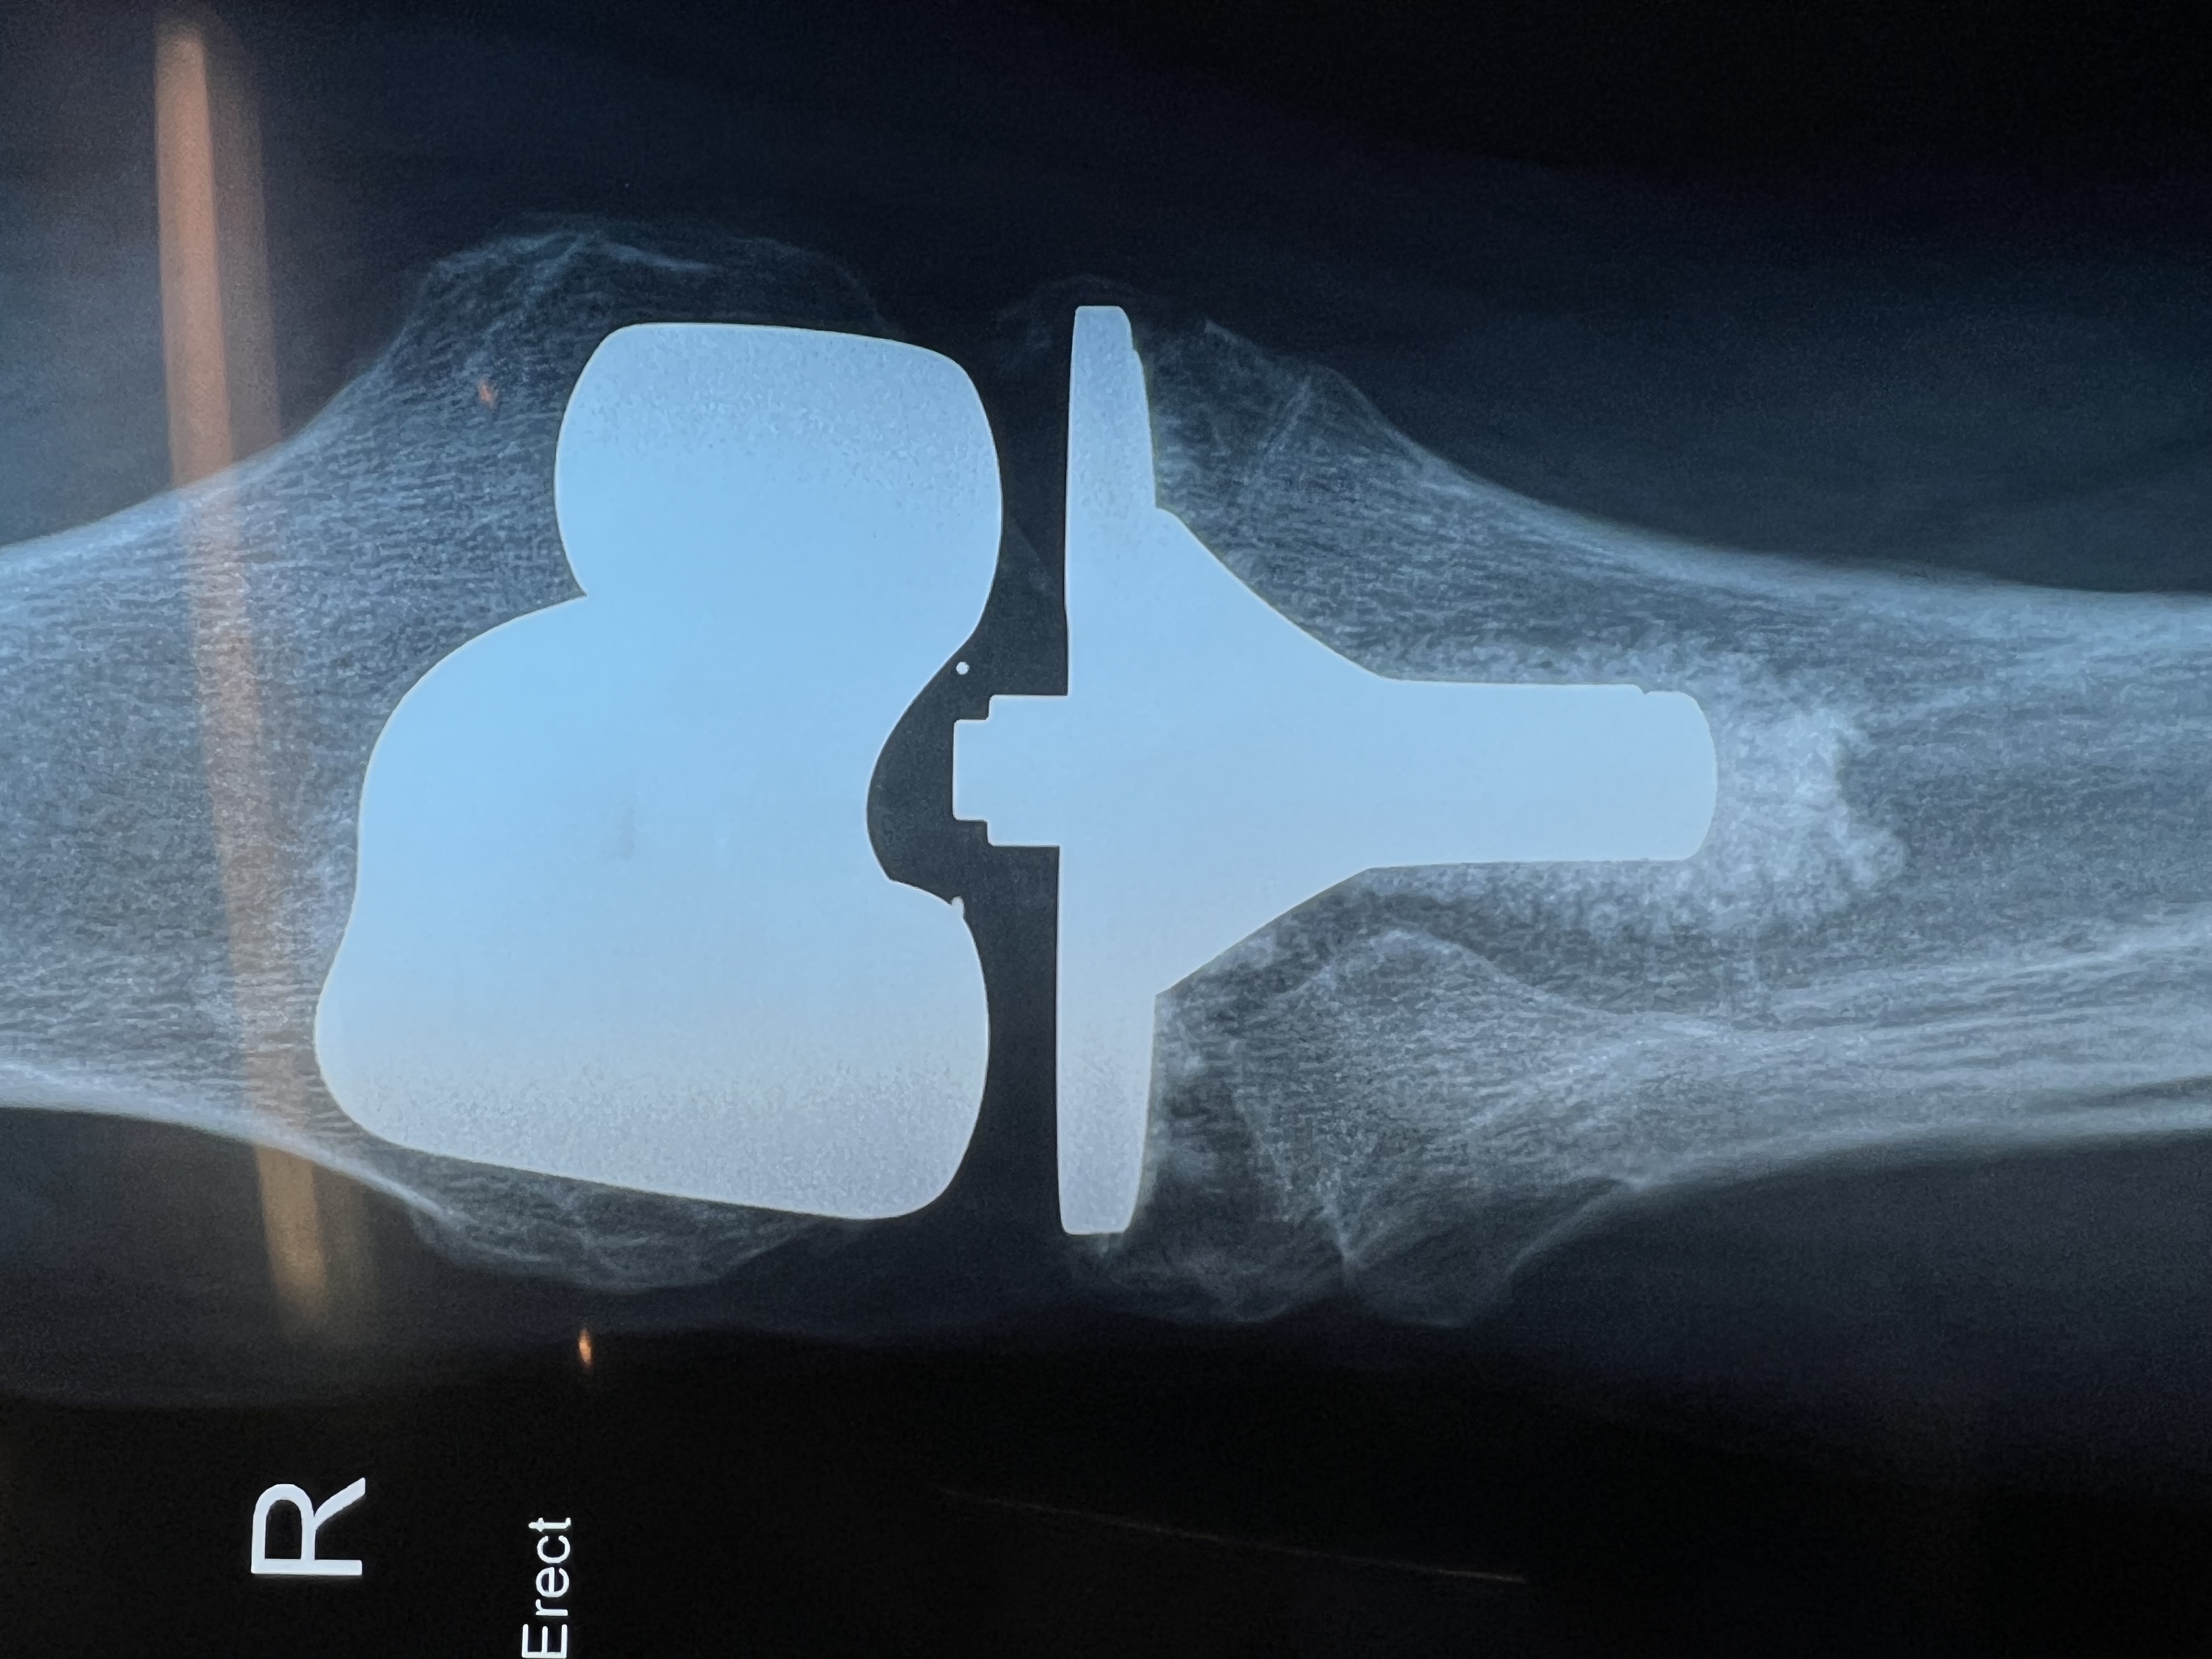

Knee TKR close B Braun AS Emotion Total Knee Replacement showing Gold ceramic coating of Zirconium Nitride

A total knee replacement is a surgery to replace a damaged or worn-out knee joint with an artificial one. It is often done for people with severe arthritis or injuries that cause chronic pain, stiffness, and difficulty walking.

1. Removes the damaged bone and cartilage from the ends of the thigh bone (femur) and shin bone (tibia).

2. Shapes the bones to fit the artificial joint.

3. Attaches the new knee joint, made of metal and plastic, to restore smooth movement.

4. Tests for proper movement and stability before closing the incision.